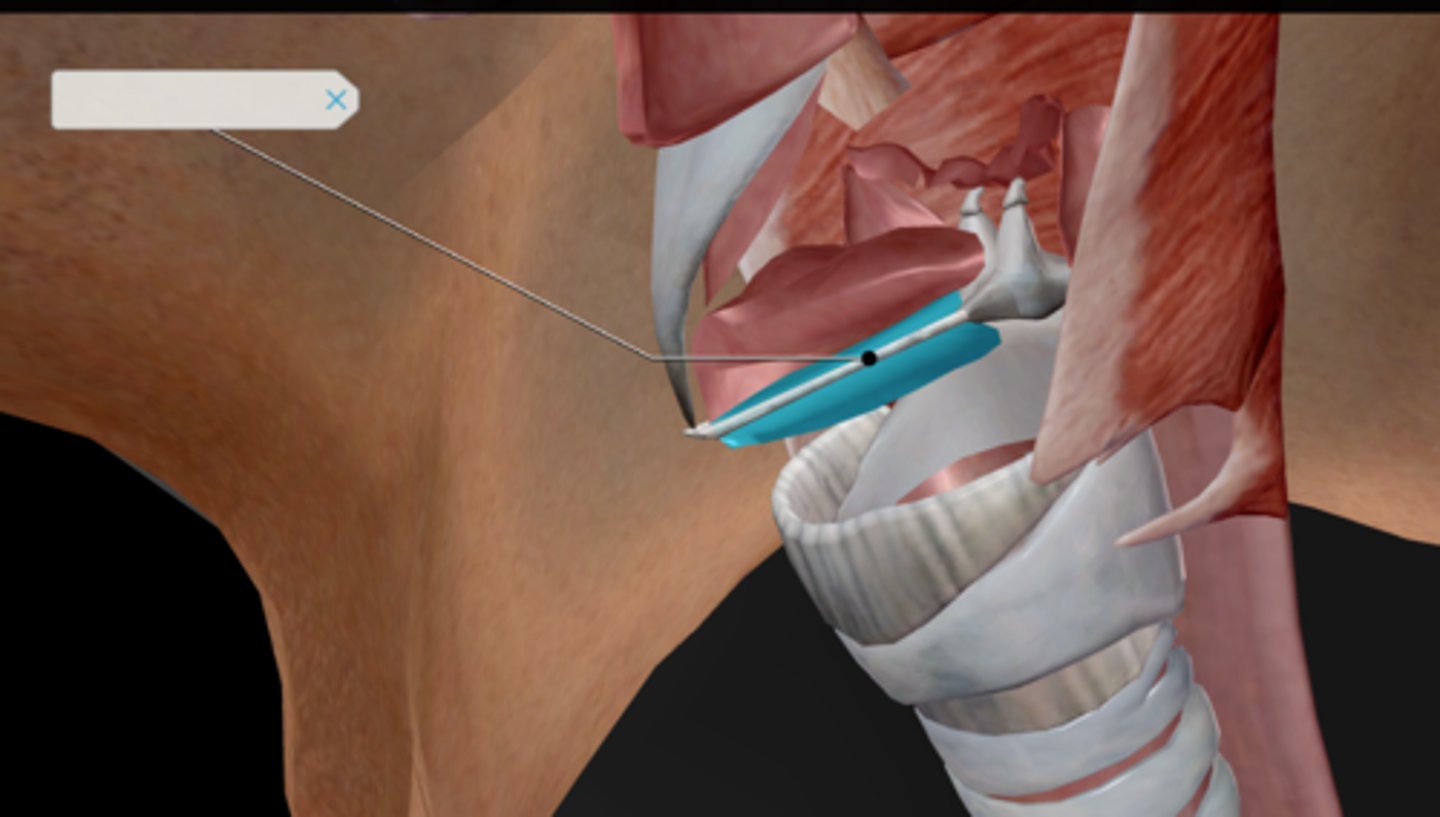

Larynx

Epiglottis

Thyroid cartilage

Cricoid cartilage

Vocal ligament

Vocal folds

Vestibular folds

Trachea

Tracheal cartilaginous rings